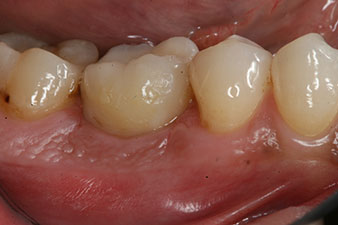

Abformung

Abb. 8: Es folgt die Abformung für die definitive Krone.

Damit konnten eine erfolgreiche Osseointegration und ausreichende biologische Stabilität dokumentiert werden, die eine Abformung in derselben Sitzung erlaubte.

Die Abschlussbilder zeigen die verschraubte monolithische Kompositkrone in situ und die Röntgenkontrolle (Abb. 9 und 10) (6).

Kompositkrone

Abb. 9: Die definitive Kompositkrone wurde im Labor auf ein PEEK-Hybrid-Abutment geklebt und kann sofort verschraubt werden.